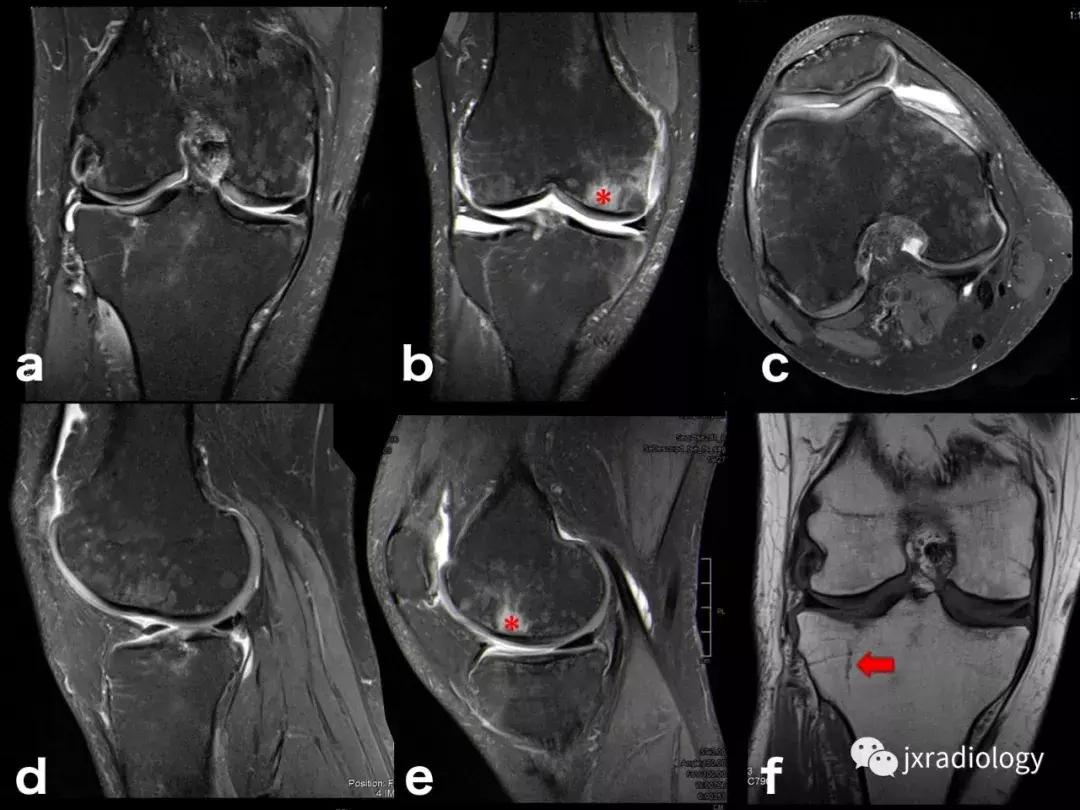

图27:废用性骨质疏松症(DO):在骨骺上的所有序列中显示的融合和斑片状中-高信号影是典型的长期固定后的短暂性骨质疏松症。恢复活动在废用骨中产生比在正常骨中更大的应力,因为必须支撑负载的骨小梁更小更弱,因此出现骨髓水肿(应力反应也在内侧髁上看到并用* 标识)。一个愈合的外侧胫骨平台骨折(箭头)。(a-e:PD-FS-WI; f:T1-WI)。值得注意的是,复杂性局部疼痛综合征(CRPS,包括包括反射*交性**感神经营养不良,痛觉神经营养不良和Sudeck骨萎缩)具有与DO相同的MRI骨水肿模式,但其病理生理学与废用脱钙无关,并且总是伴有疼痛(DO是无症状患者的偶然发现,在有外固定的患者中)。